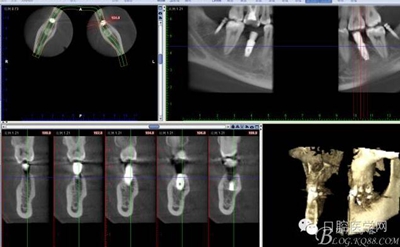

CT